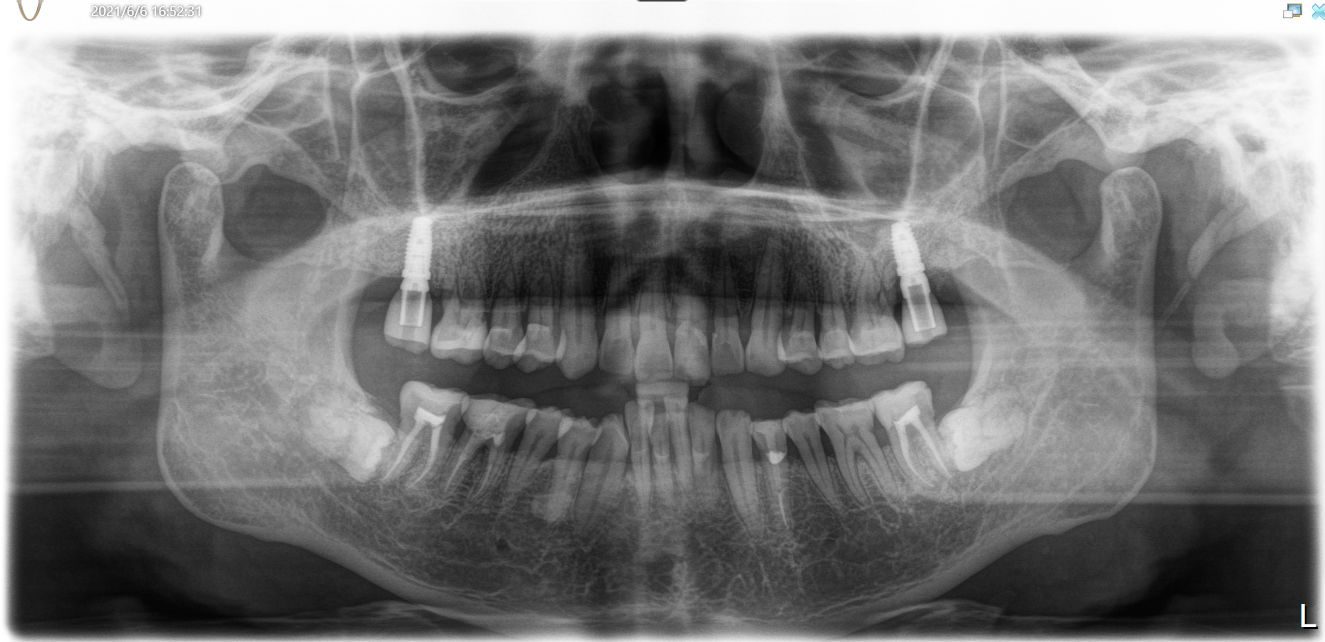

患者是成功人士,平时非常忙碌,忽略了口腔健康,直到有一天无法咀嚼食物后才想到要治疗牙齿,我们为他摄了CBCT,发现有重度牙周病,上合双侧7自然脱落,左上8,III度松动,并近中倾斜移位,对合牙严重伸长,还有其他牙齿疾患,需要综合治疗;经过牙周病治疗、上合窦骨增量、上合种植修复、拔牙、截冠、根管治疗、桩冠、高嵌体修复等!时间长达一年,终于恢复了正常牙列!可以享受食物的美好!